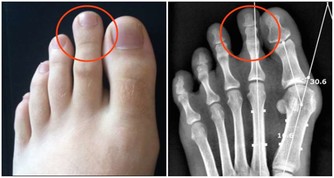

在臨床上,經常能看到患有腎結石的人,但是患者本人往往意識不到,腎結石的常見臨床表現有哪些呢?

最常見的就是腰部疼痛,這種疼包括絞痛或者鈍痛,不要總認為腎結石的疼痛總是很劇烈,當結石還沒有下落到輸尿管的時候,所導致的疼痛往往不會非常劇烈。

除此之外,結石可能會損壞腎的微小血管,造成血尿,某些人還會表現為尿頻、尿急和尿痛等。